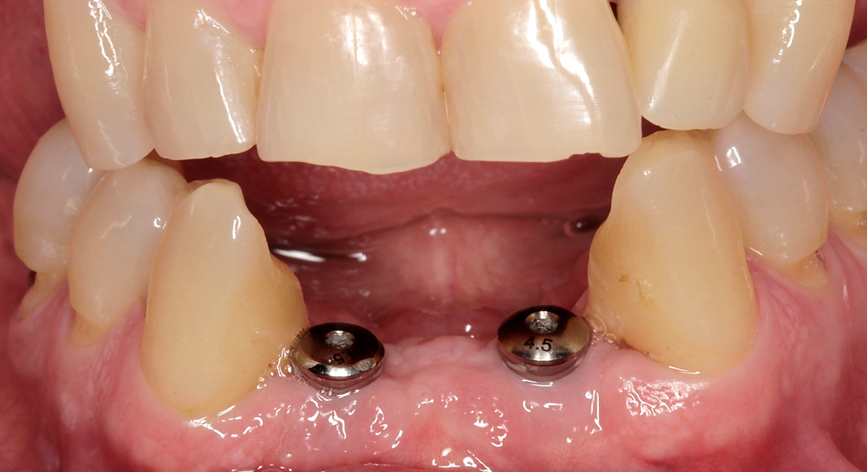

Um paciente procurou tratamento protético reabilitador com queixa dos dentes 31 e 41 que estavam abalados. Ao exame clínico e radiográfico, notou-se mobilidade dos dentes, doença periodontal ativa e perda óssea.

Avaliamos o espaço mésio-distal entre os dentes 33 e 43 e constatamos a ausência de distância para a colocação de implantes individualizados. Assim sendo, optamos pela instalação de dois implantes Veloce CM de diâmetro 3.3 e pilares do tipo micro-cônico para a solução clínica.

Dessa forma, na matéria desta semana, será abordada uma situação clínica de espaço mésio-distal restrito com o uso de implantes híbridos do tipo Veloce CM estreitos de 3.3 de diâmetro e posterior confecção de prótese sobre implantes com pilares intermediários do tipo micro-cônico.